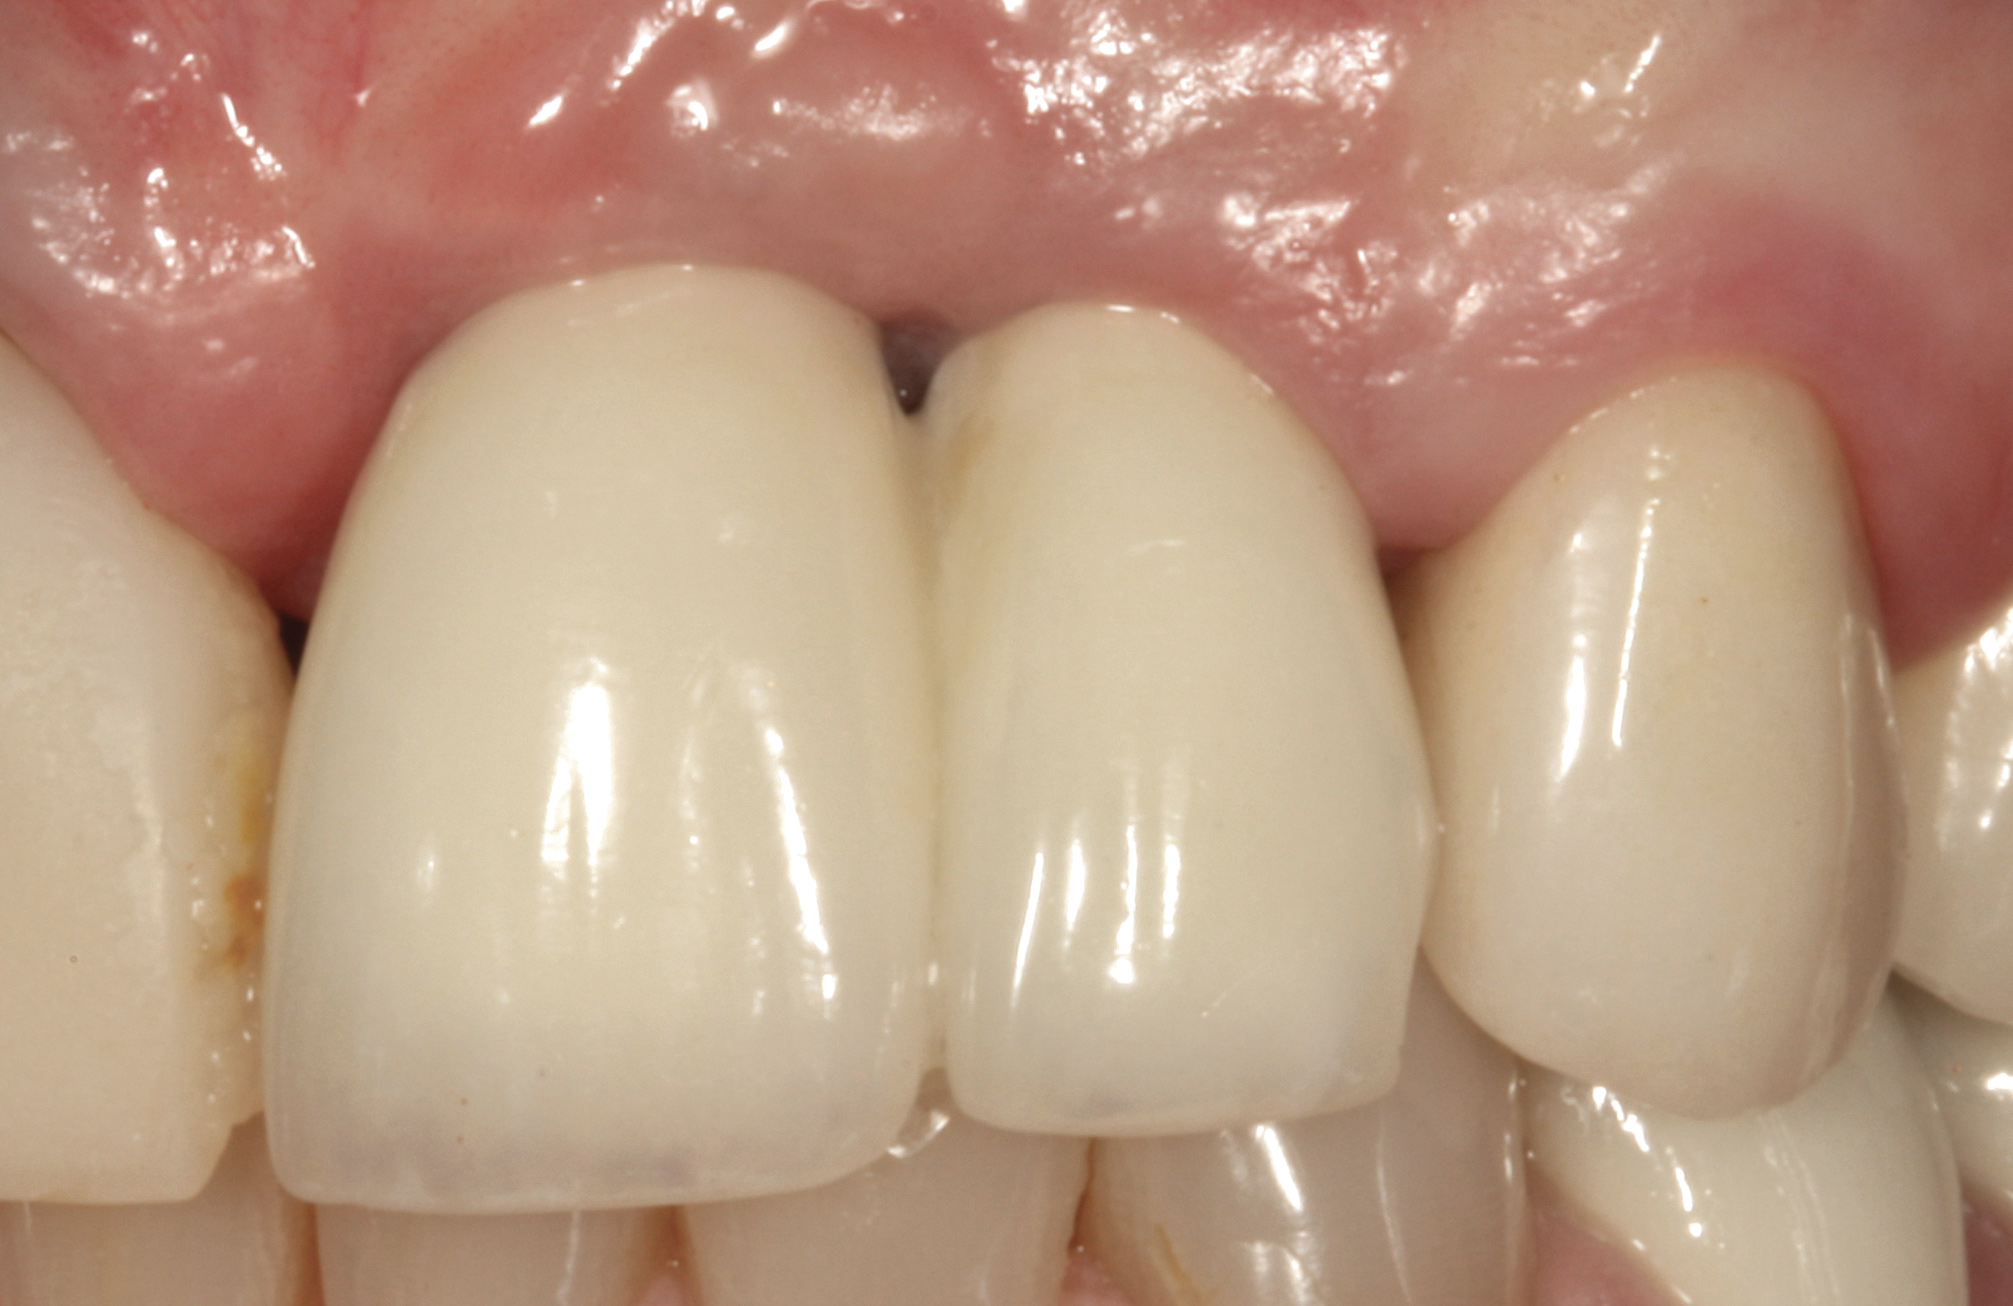

Problem: Two adjacent implants are located in the central–lateral incisor positions, and the patient has a high smile line along with loss of inter-implant papilla and midfacial recession around both implants (Figure 29 and Figure 30).33-38

Fig 1. Midfacial recession can affect the esthetics of a smile and lead to an unsatisfactory outcome.

Fig 2. The cause for midfacial recession is excessive labial implant placement. Secondary to poor placement is overcontouring of the implant abutment.

Fig 29. Two adjacent implants placed in the esthetic zone can lead to loss of the interdental papilla and a negative outcome for a patient with a high smile line.

Fig 30. The intraoral view of the loss of the interdental papilla between teeth Nos. 9 and 10.